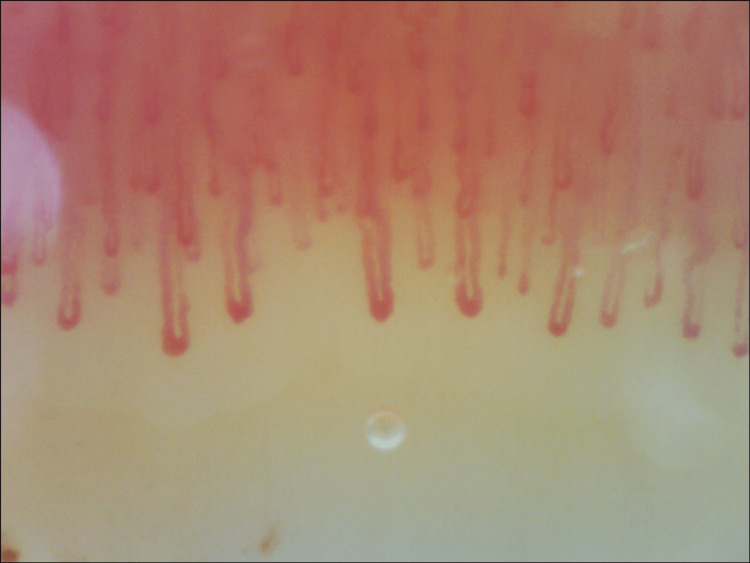

To investigate a possible underlying cause for this Raynaud’s phenomenon, further tests were requested. Complete blood cell count and biochemistry with muscle enzymes were normal. There were no vitamin or iron deficiencies. Thyroid hormones were within normal range. Laboratory tests were negative for antinuclear antibodies, as well as anti-double-stranded DNA (anti-dsDNA), anti-centromere, anti-SCL-70, anti-RNA polymerase III, anti-ribonucleoprotein (anti-RNP), anti-La/Sjogren’s syndrome B (SSB), and anti-Sjogren’s syndrome A (SSA)/Ro antibodies. Immunoglobulins and complement levels were within normal limits. Serological tests were negative for hepatitis virus B and C, human immunodeficiency virus (HIV), herpes simplex virus (HSV), Epstein-Barr virus (EBV), Chlamydia trachomatis, Borrelia, Rickettsia, and Coxiella. Interferon-gamma release assay (IGRA) was also negative. Chest X-ray showed no abnormalities, lung function tests were normal, and chest, abdominal, and pelvic computed tomography showed no malignancy or other pathological findings that could justify a paraneoplastic RP. Magnetic resonance excluded sacroiliitis, and no inflammatory activity was identified in the PET scan. Subclavian Doppler ultrasound showed normal filling of the lumen, and the Doppler study was normal. Nailfold capillaroscopy (Figure 2) revealed non-specific changes bilaterally, such as capillary enlargement (34-49 microns), without megacapillaries, rare capillary tortuosity, a few small traumatic hemorrhages, and pericapillary edema, with normal density (10 capillaries/mm2) and no avascular areas. These changes were compatible with a non-scleroderma-like pattern.

Figure 2. Nailfold capillaroscopy before treatment.

One-year follow-up capillaroscopy (Figure 4) showed significant improvement in capillary enlargement and less tortuosity, with most capillaries being normal in shape and size.

Figure 4. Nailfold capillaroscopy after treatment.